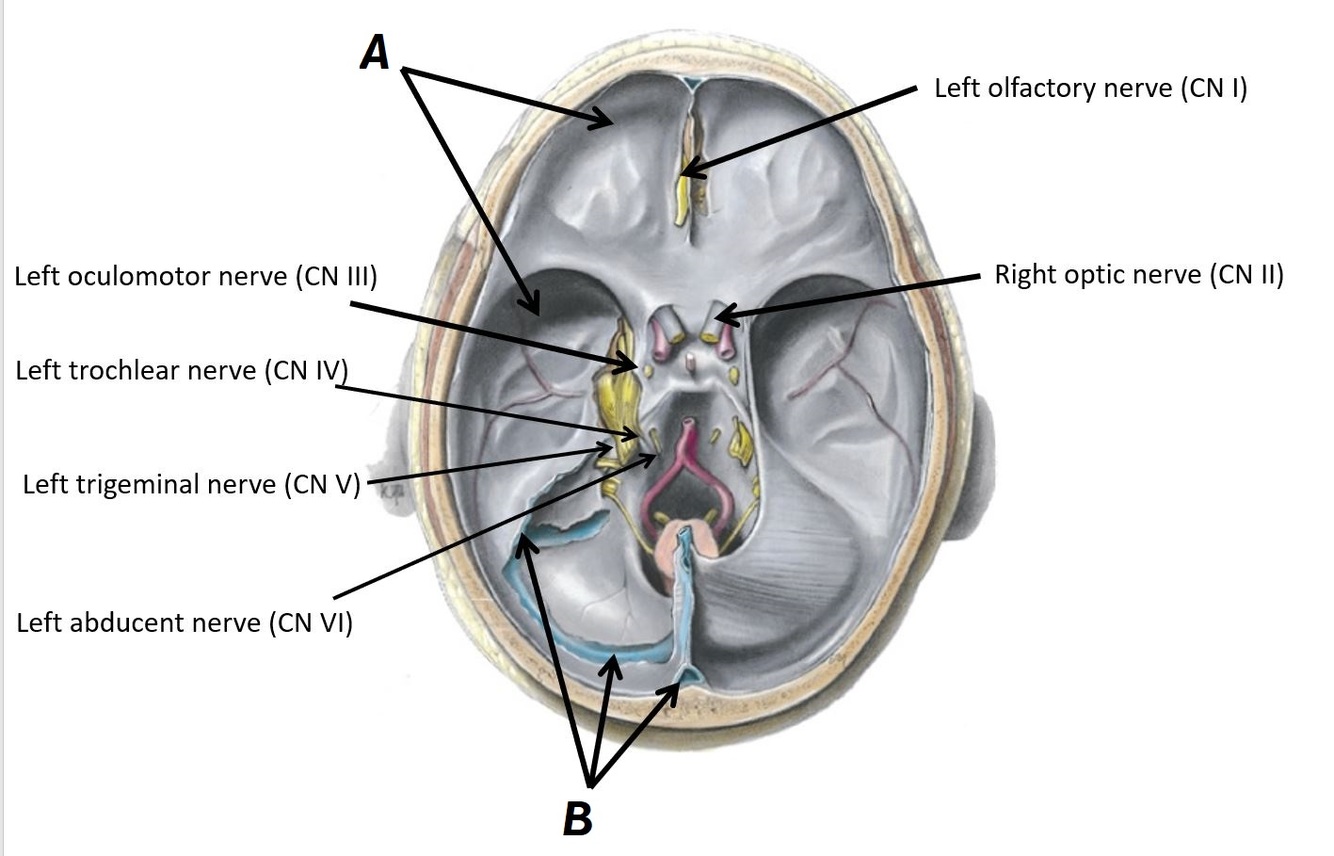

Name structures A and B

A - Dura mater

B - Tentorium cerebelli

Name structures A, B and C

A - Anterior intercavernous fossa

B - Left cavernous sinus

C - Dural venous sinuses